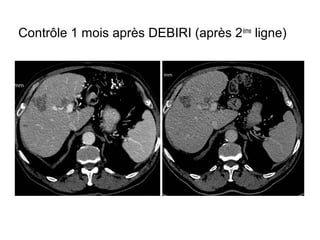

Contrôle 1 mois après DEBIRI (après 2ème

ligne)

Contrôle 1 moisaprès DEBIRI (après 2ème ligne)